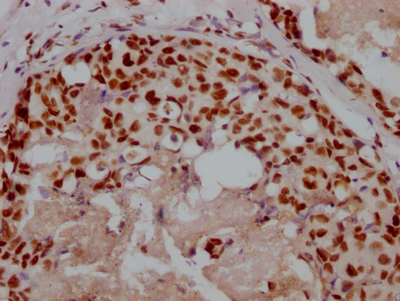

IHC image of CSB-PA892485ESR1HU diluted at 1:50 and staining in paraffin-embedded human endometrial cancer performed on a Leica BondTM system. After dewaxing and hydration, antigen retrieval was mediated by high pressure in a citrate buffer (pH 6.0). Section was blocked with 10% normal goat serum 30min at RT. Then primary antibody (1% BSA) was incubated at 4°C overnight. The primary is detected by a Goat anti-rabbit polymer IgG labeled by HRP and visualized using 0.05% DAB. Secondary antibody only control: uses 1% BSA instead of primary antibody